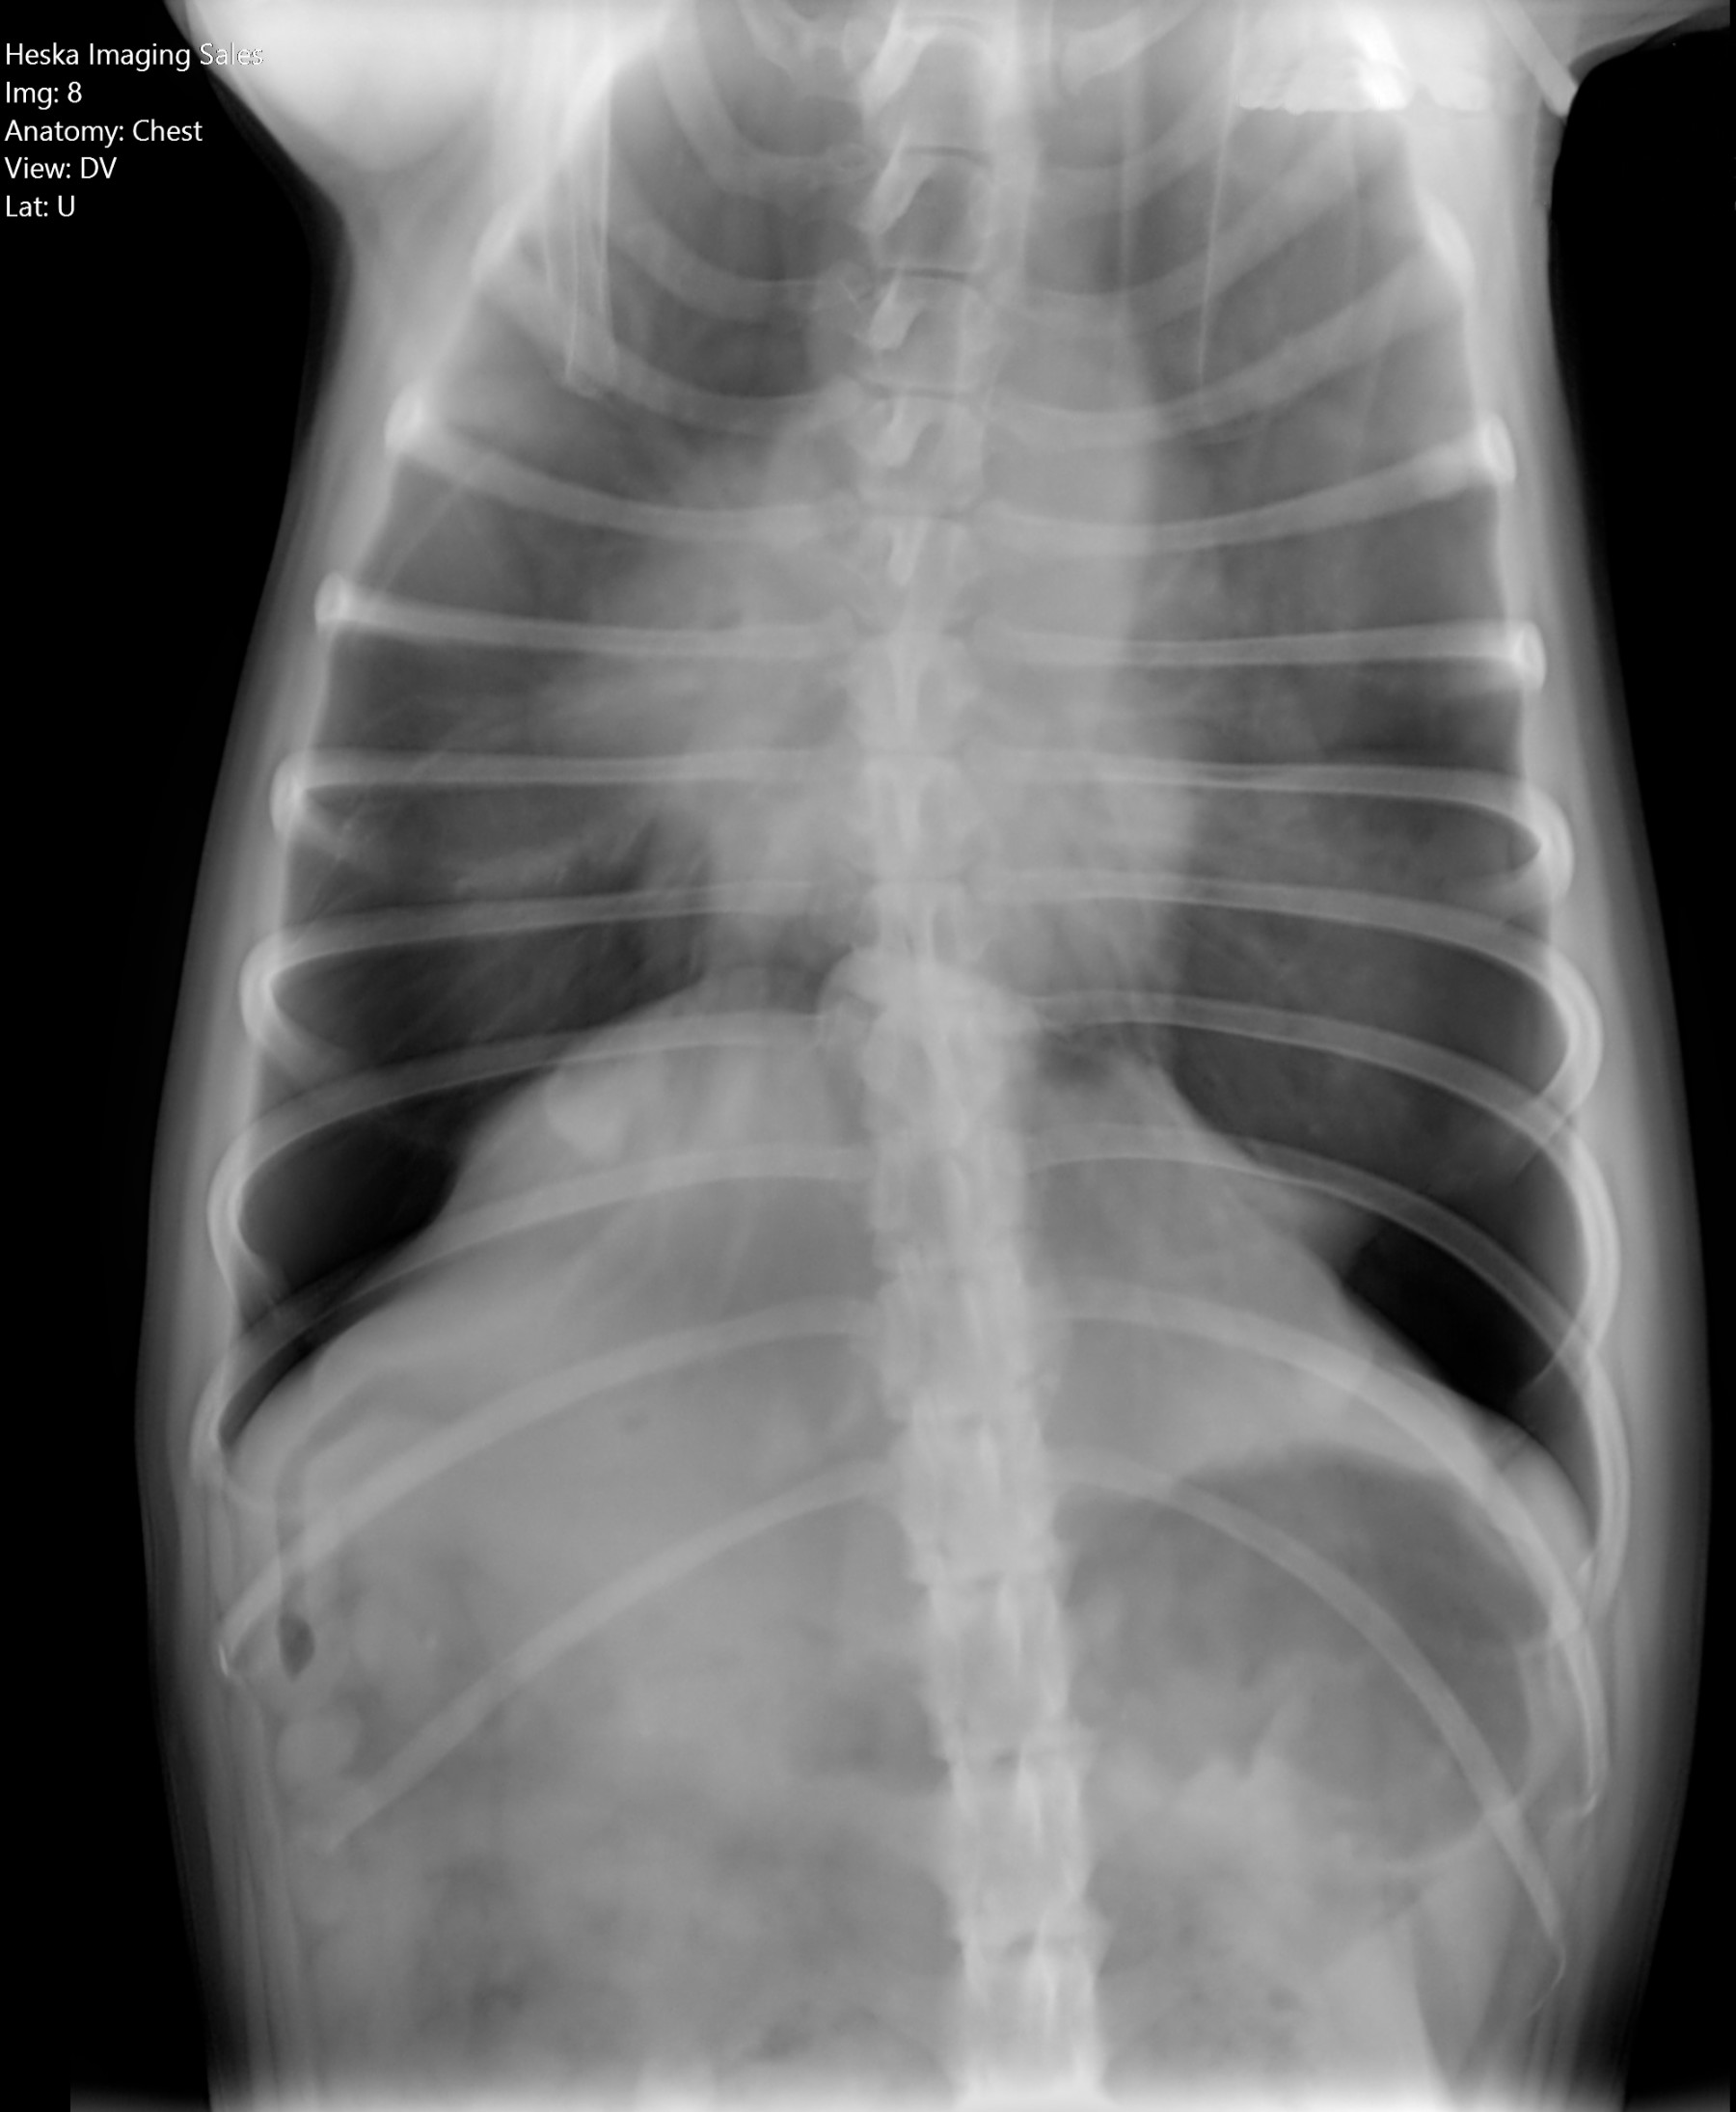

Cambios Térmicos en las Extremidades de Caballos,

Asociados a Golpes y su Evaluación por Termografía.

Los caballos de salto, en competencia, pueden derribar obstáculos y lastimarse. Si se golpean, no siempre claudican. Considerando al calor como un signo de inflamación, se evaluaron los cambios térmicos de 6 áreas de las extremidades torácicas y pelvianas de 23 caballos de salto en nivel de competencia de 1.05 a 1.60 m de altura, por medio de termografía durante 4 días de competencia (N=2208 áreas).